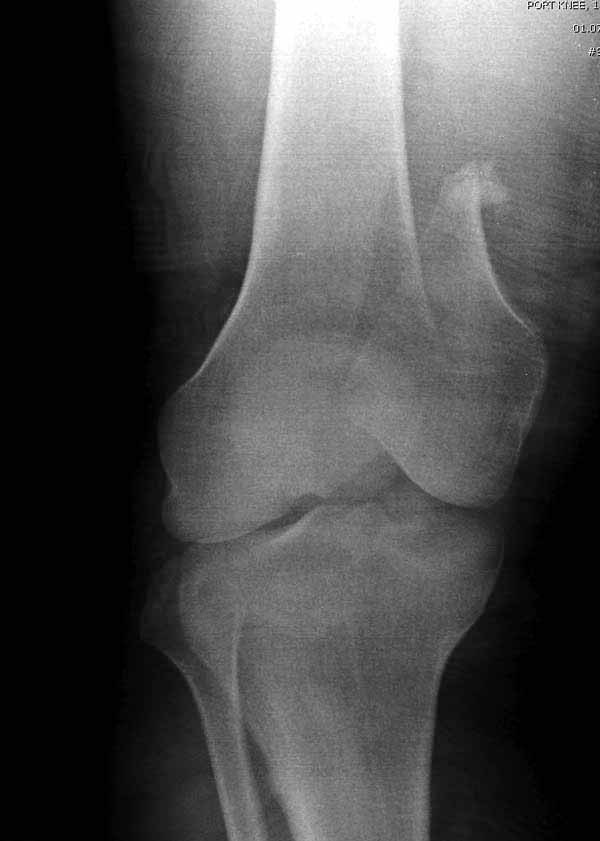

Представленный снимок не дает полную информацию. Там вроде простой перелом, но на самом деле, кроме смещенного (латерального, возможно медиального?) мыщелка на второй проекции имеется медиальный короткий дистальный фрагмент в флексии. Надо было сделать прямой снимок с захватом малоберцовой, который ориентировал бы стороны. Без КТ обычный снимок в дистракции поможет разобраться в топографии фрагментов.

Во время фиксации надо соблюдать осторожность, особенно с коротким фрагментом на другой стороне. Обычно на прямой проекции трудно заметить флексионную деформацию мыщелка и упускается адекватная фиксация. Без пластины винты не смогут удержать, и мыщелок на второй стороне может сместиться. Для фиксации надо развернуть мыщелок и удержать винтами. Качество межмыщелковой репозиции надо проконтролировать артротомией. Из всех доступов только передне-латеральный доступ (Swashbuckler) даст обзор для ревизии качества фиксации, который в будущем может быть использован для артропластики.

Кстати, из вашего снимка, если отмечены вашим рентгенологом правильно, тогда получается снимок левого колена, и, соответственно, длинный переходящий в диафиз мыщелковый фрагмент находится медиально. Если так, тогда меняется сценарий фиксации!!!

Сразу не обратил ваше внимание именно на это, что сломаны оба мыщелка, и больший является именно медиальным мыщелком, а пластины ставятся по латеральной стороне, соответственно, в этом медиальном мыщелке от пластины останутся только концы винтов, которые не обеспечат достаточной фиксации мыщелка.

И не обратите, коллега, пока не сделаете четкие анфасные снимки (лучше с дистракцией) где будет четко визуализироваться малоберцовая кость. Думается, что и КТ здесь будет уместно, дабы не пропустить возможное флексионное повреждение (перелом Hoffa).

По прямому снимку репозиция удалось, поздравляю! А с латеральной стороны подозрение на флексионный компонент латерального мыщелка остается, а снимок получился косым, надо было бы повторить.

Выбор имплантов не совсем удачный, подкожно выступающие болты в мыщелках вскоре могут привести к проблемам. Вместо солитарной фиксации болтом-стяжкой дистально можно было бы добавить пару винтов, которые создали бы ротационную стабильность и межфрагментарную компрессию.